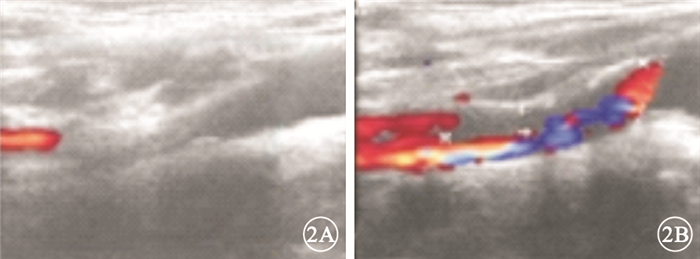

圖3

左眼治療5 d后彩色眼底像。視網膜顳上支動脈及靜脈管徑較前增粗,顳上支動脈主干分叉處的2個節段狀黃白色反光灶變小,其遠端小分支動脈閉塞區可見部分小分支動脈(白箭) 圖 4 左眼治療5 d后FFA像。4A.24.3 s,視網膜靜脈充盈,顳上支靜脈顳支仍無灌注;4B.27.9 s,顳上支靜脈顳支開始充盈;4C.38.9 s,顳上支靜脈顳支充盈完全

圖3

左眼治療5 d后彩色眼底像。視網膜顳上支動脈及靜脈管徑較前增粗,顳上支動脈主干分叉處的2個節段狀黃白色反光灶變小,其遠端小分支動脈閉塞區可見部分小分支動脈(白箭) 圖 4 左眼治療5 d后FFA像。4A.24.3 s,視網膜靜脈充盈,顳上支靜脈顳支仍無灌注;4B.27.9 s,顳上支靜脈顳支開始充盈;4C.38.9 s,顳上支靜脈顳支充盈完全

圖3

左眼治療5 d后彩色眼底像。視網膜顳上支動脈及靜脈管徑較前增粗,顳上支動脈主干分叉處的2個節段狀黃白色反光灶變小,其遠端小分支動脈閉塞區可見部分小分支動脈(白箭) 圖 4 左眼治療5 d后FFA像。4A.24.3 s,視網膜靜脈充盈,顳上支靜脈顳支仍無灌注;4B.27.9 s,顳上支靜脈顳支開始充盈;4C.38.9 s,顳上支靜脈顳支充盈完全

圖3

左眼治療5 d后彩色眼底像。視網膜顳上支動脈及靜脈管徑較前增粗,顳上支動脈主干分叉處的2個節段狀黃白色反光灶變小,其遠端小分支動脈閉塞區可見部分小分支動脈(白箭) 圖 4 左眼治療5 d后FFA像。4A.24.3 s,視網膜靜脈充盈,顳上支靜脈顳支仍無灌注;4B.27.9 s,顳上支靜脈顳支開始充盈;4C.38.9 s,顳上支靜脈顳支充盈完全